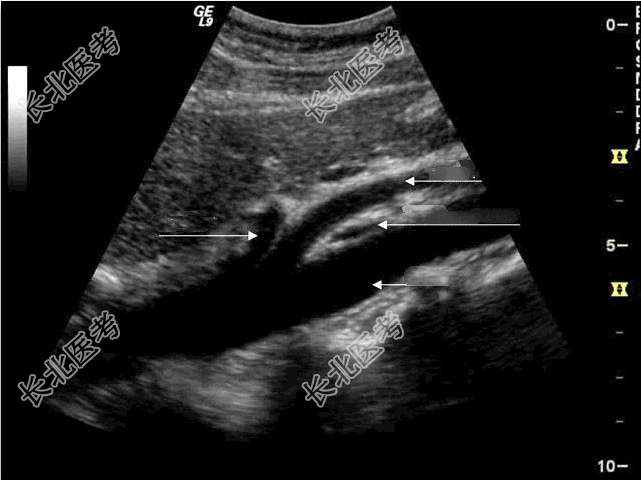

- 单项选择题胡桃夹综合征是什么?超声检查如图

A、肠系膜上静脉受压迫综合征

B、下腔静脉受压迫综合征

C、左肾静脉受压迫综合征

D、右肾静脉受压迫综合征

E、肠系膜下静脉受压迫综合征